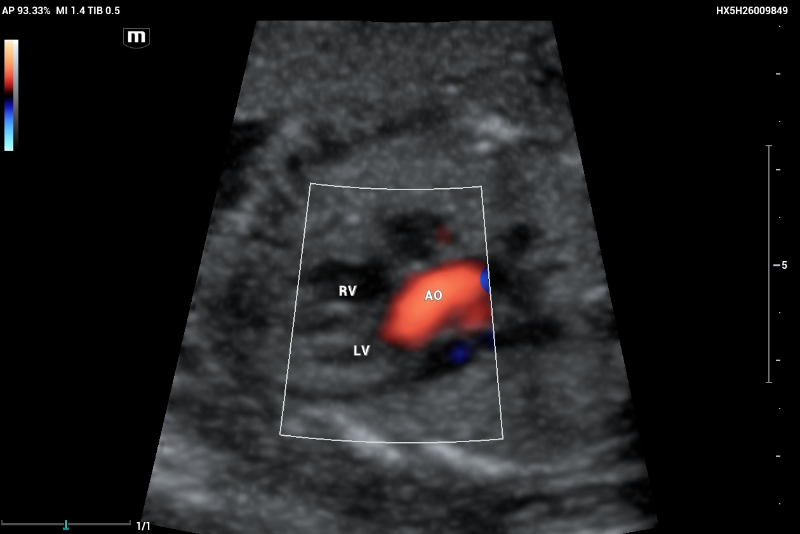

An example of normal echocardiography performed on Mindray Resona I9 system.  Artery–ventricle concordance showing the aortic outflow tract (AO) emerging of the left ventricle (LV)

Figure 5. An example of normal echocardiography performed on Mindray Resona I9 system. Artery–ventricle concordance showing the aortic outflow tract (AO) emerging of the left ventricle (LV)